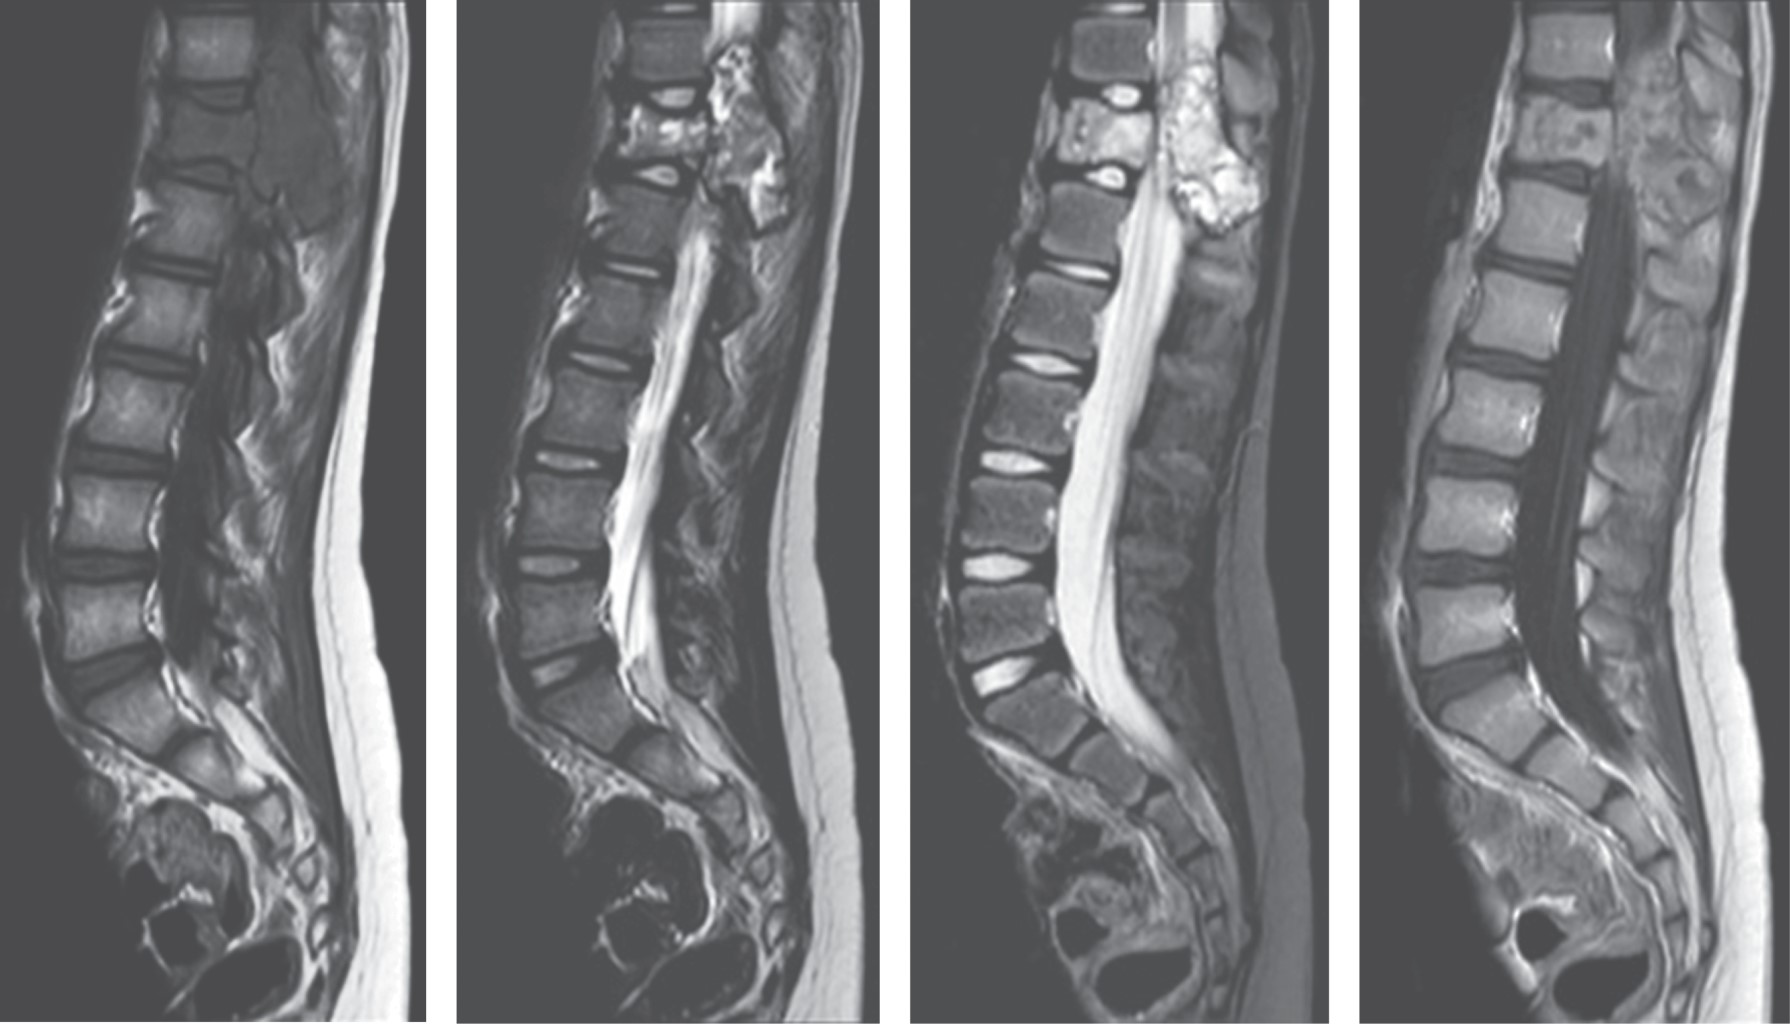

La RM simple y contrastada caracterizó de mejor forma lesión, siendo extradural, heterogénea, con una porción multilocular con niveles líquido-líquido observados hiperintensos en T2; presentaba también una porción sólida que realzaba al contraste, la cual invadía al canal medular generando invasión anteriormente hacia el cuerpo vertebral, con destrucción del pedículo, proceso transverso y la lámina (Figuras 2, 3, 4, 5 y 6).

Durante el seguimiento a 12 meses presentó una recuperación de la sensibilidad en ambas extremidades inferiores y de la fuerza a 4+/5 bilateral, así como una normorreflexia. El diagnóstico prequirúrgico, basado en la clínica y los estudios radiológicos inicialmente fue de un osteosarcoma telangiectásico, no obstante, con el resultado histopatológico se hizo el diagnóstico definitivo de quiste óseo aneurismático.